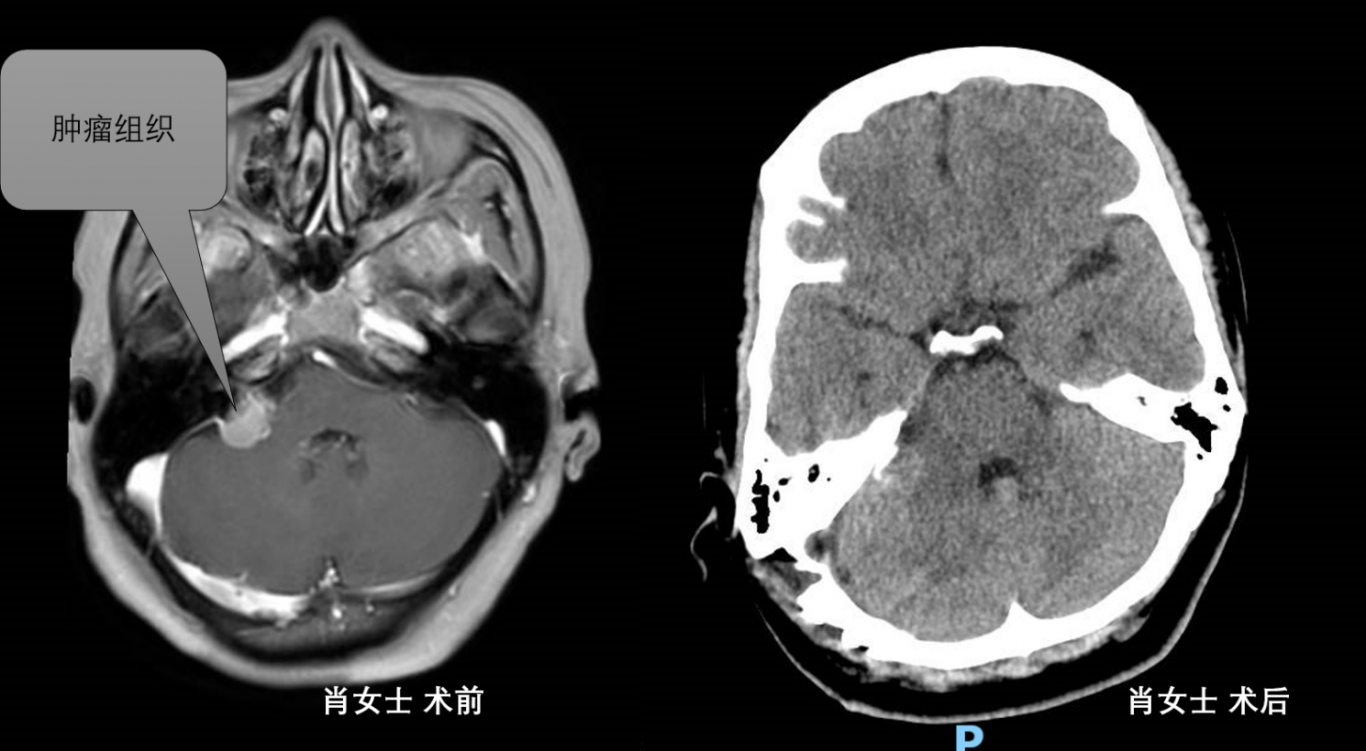

在華西專家劉雪松教授的協(xié)助下,市中醫(yī)醫(yī)院神經(jīng)外科采用顯微鏡下切除顱底腫瘤術(shù),先后成功為羅女士、肖女士、唐女士治療了腦內(nèi)頑疾。

江陽(yáng)區(qū)肖女士,因反復(fù)頭疼長(zhǎng)達(dá)5年入院,頭顱MRI提示右側(cè)橋小腦角占位性病變。術(shù)后病檢提示神經(jīng)鞘瘤,術(shù)后2周,患者好轉(zhuǎn)出院。